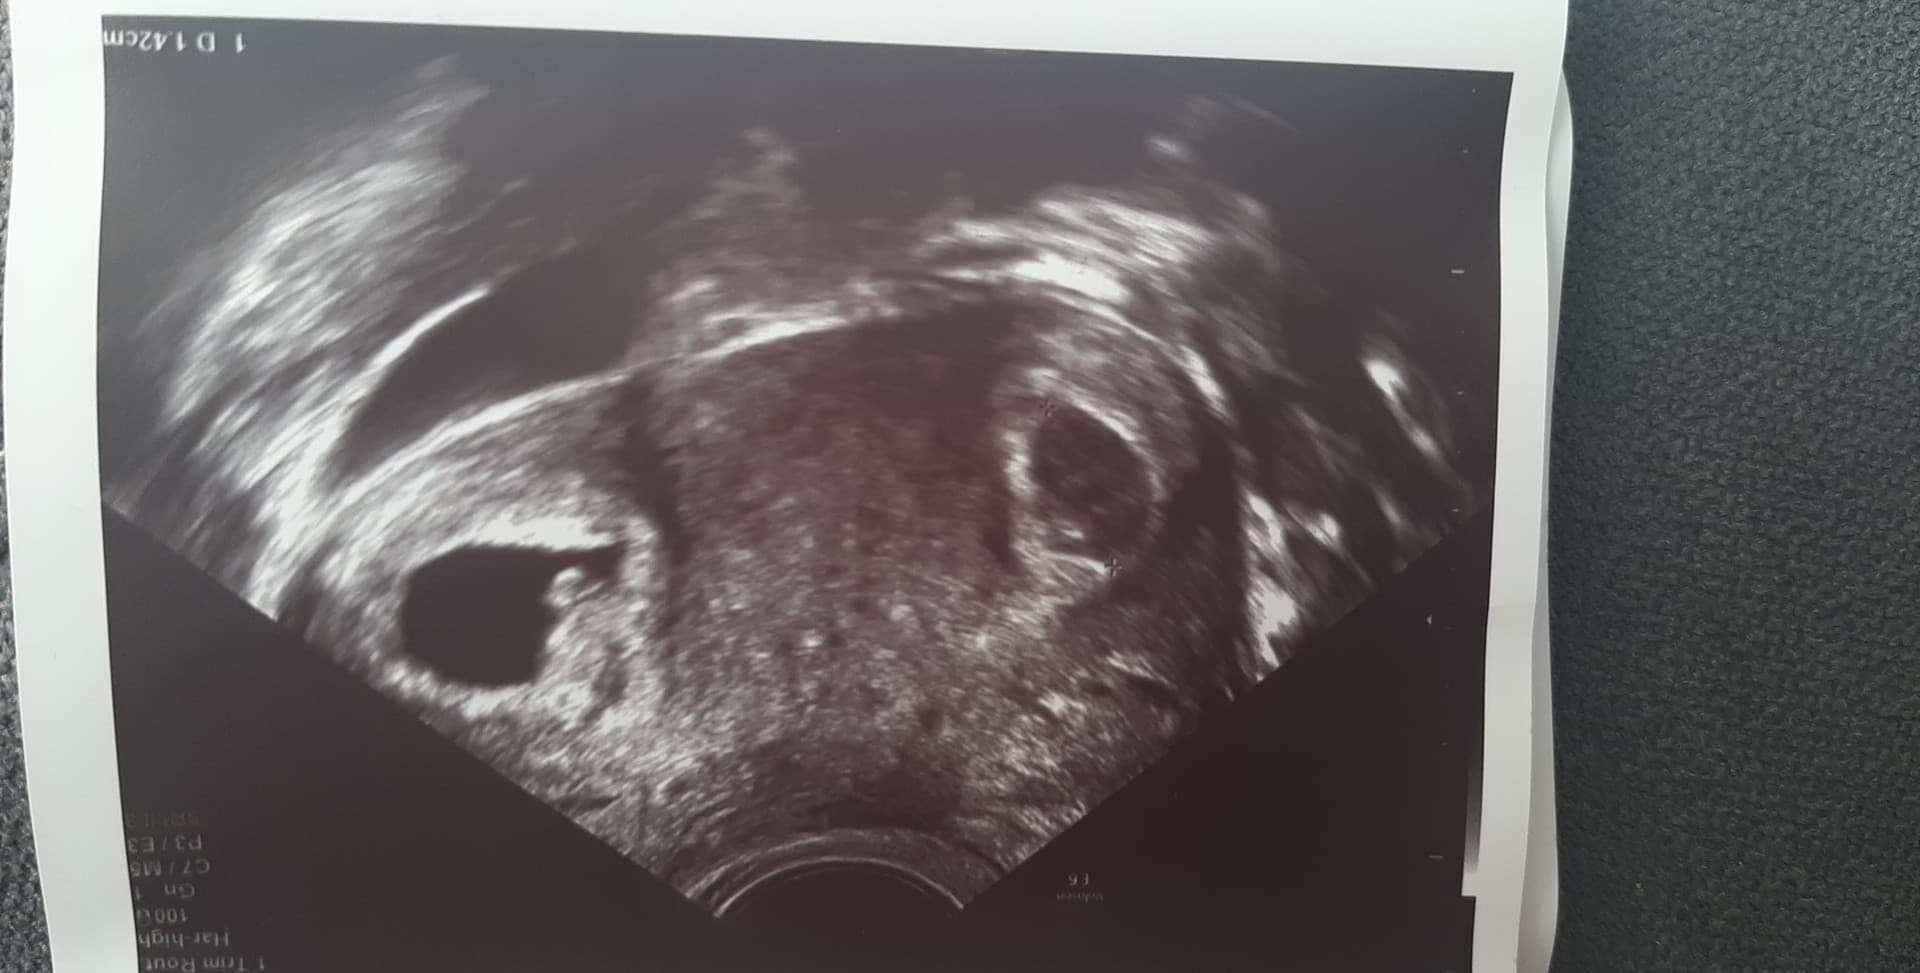

Dziewczyny, ja też po wizycie... podobne info... jeden zarodek jest już widoczny, serduszko bije, ale pojawił się drugi pęcherzyk.... Boże, żeby tylko było wszystko dobrze.... jaja

coś ty, w szoku jestem 🙈 jedynie na początku jak badałam progesteron z przyrostem bety to był dość wysoki bo 44,8 i przeszukałam pół internetu i właśnie jedna z opcji wysokiego proga była ciąża bliźniacza. Fotkę mam, ale nie umiała ginka znaleźć takiego kadru żeby było widać dwa zarodki na raz wiec nie jest jakaś oczywista, ale słyszałam dwa serduszka dwóch małych myszek 💖💖 ogólnie byłam tak zaskoczona, zaczęłam płakać, śmiać się i trząść (jeszcze z ta głowica w środku), z wrażeń zapomniałam zadać tylu pytań. Ale następna wizyta w Dzień Dziecka za 3 tygodnie, powinnam być już bardziej skoncentrowana 💫

Ja jestem po in vitro... mialam podany 1 zarodek, ostatnio na wizycie był 1. A dzis poszłam z tym plamieniami, a ginka się mnie pyta 'ile pani miala podanych zarodkow?' Mowie jeden.. a Ona a są dwa :D 😀 kosmos... jeden jest już ladnie widoczny z serduszkiem, wszystko ok, natomiast drugi dopiero pojawił się pechezryk i nie jest pewna, czy coś jest w środku... za tydzień kolejna wizyta to się okaże, czy rozwijają się obydwa ❤ oby tylko nie było żadnych komplikacji, bo teraz tego się obawiam